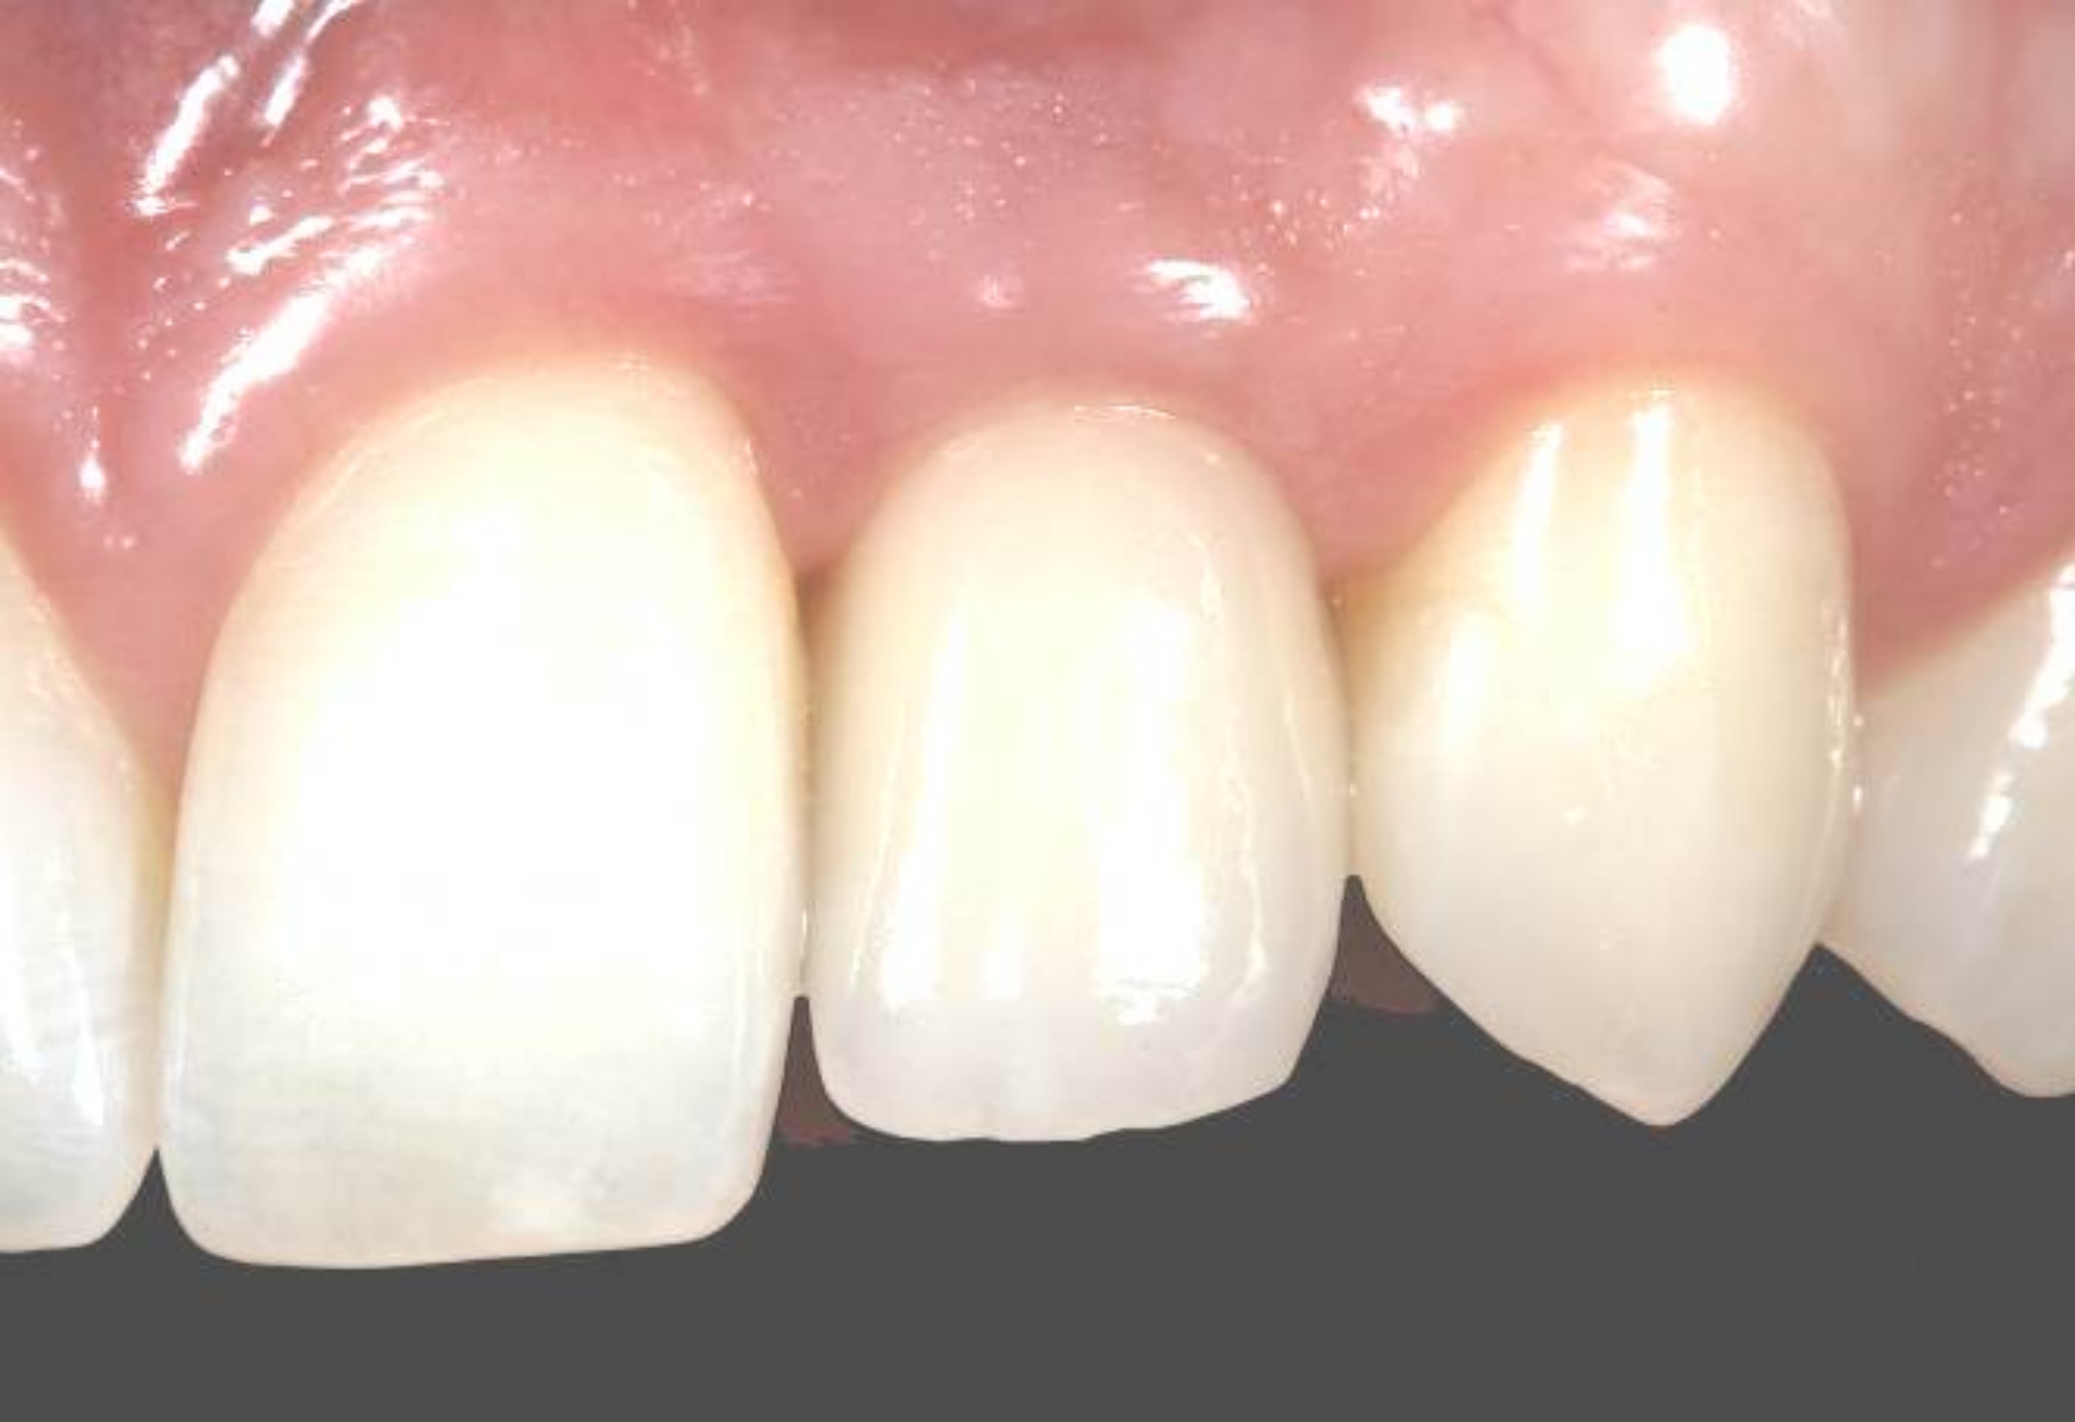

Fig 18. The final restoration after 4 months.

Figure 18

Fig 25. The final crown in place 6 months after implant insertion.

Figure 25